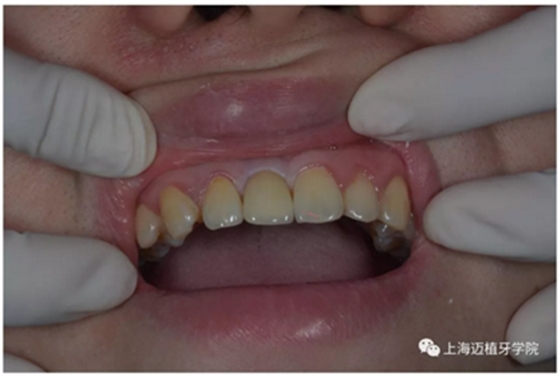

戴牙 最終修復(fù)效果